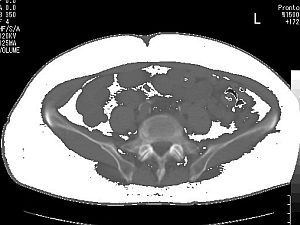

- 当院のCTで、皮下脂肪型肥満、内臓脂肪型肥満の診断ができます

下図はその実例です

| 皮下脂肪型肥満 | 内臓脂肪型肥満 |

- 内臓脂肪(白い部分)の面積100平方cm以上が、

メタボリックシンドロームの診断基準です